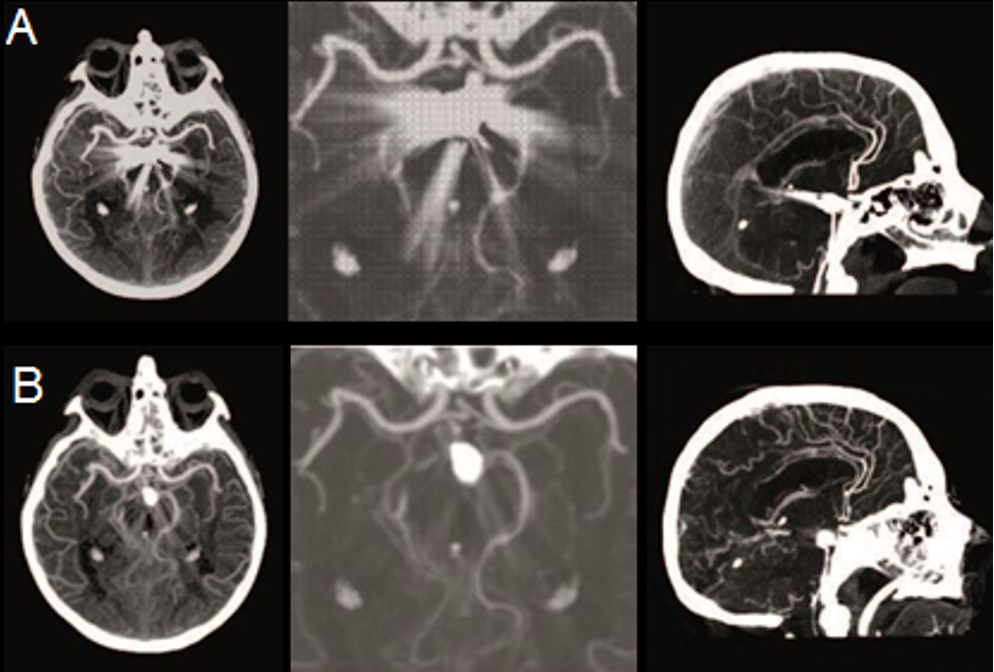

- Công nghệ AsiR-V giúp giảm độ nhiễu, tăng cường khả năng phát hiện tổn thương với liều thuốc cản quang thấp hơn, có giá trị lâm sàng trong bệnh lý đột quỵ, chấn thương. Tối ưu hóa liều tia X cho từng bệnh nhân, tự động điều chỉnh liều cho các cơ quan nhạy cảm với tia X như mắt, vú mà không giảm chất lượng hình ảnh.

Hình 5. Hình ảnh chụp CLVT mạch máu não sau đặt coil

A: Hình ảnh chụp CLVT thường quy; B: Hình ảnh chụp CLVT 512 dãy sử dụng công nghệ giảm nhiễu ảnh kim loại